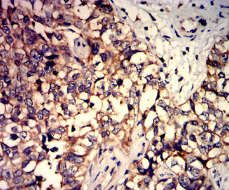

C5AR2 Mouse Monoclonal antibody[6C1G10]

Species Reactivity:    Human

IHC    1/200 - 1/1000